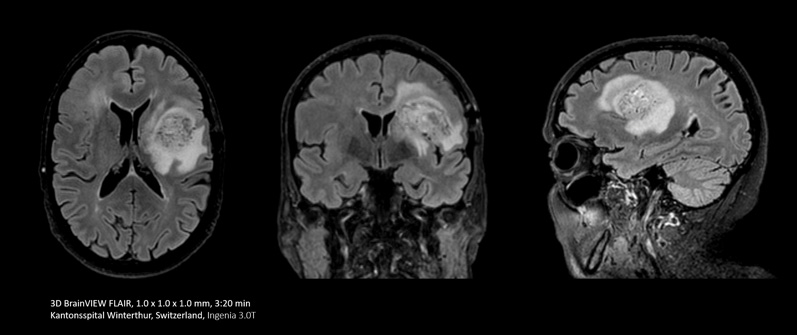

In some cases, like brain and spine examinations, it can be useful to use the power of Compressed SENSE to trade 2D MRI scan sequences for faster 3D sequences. This can allow clinicians to achieve high spatial resolution in tiny nerves and vessels.

With Compressed SENSE you can replace your single orientation 2D FLAIR scan with a multi-orientation 3D volumetric FLAIR scan in only 3 and a half minutes scan time.

I do a lot of brain imaging, and we used to do the FLAIR sequence using a 5 mm thick slice. Now with Compressed SENSE we are able to take a 3D volumetric scan for about 6 minutes down to maybe 3 and a half minutes.”

Dr. Mark Oswood, MD, PhD, Neuroradiologist, Hennepin Healthcare, Minneapolis, USA